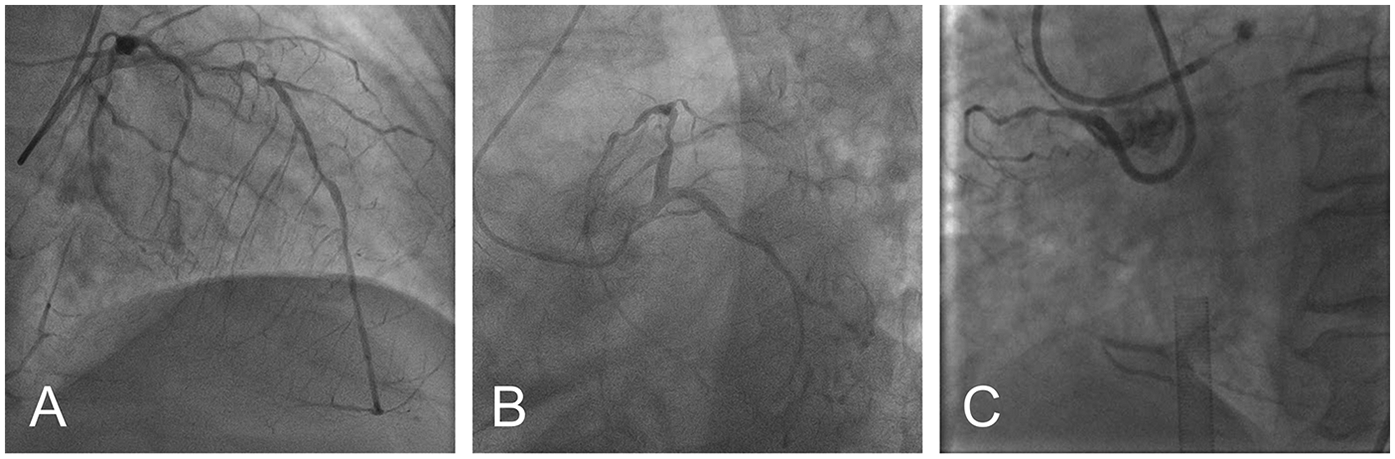

Based on these findings, the patient was diagnosed with severe AS, acute myocardial infarction, Killip III, and acute heart failure. Subsequently, the patient was provided with non-invasive positive pressure ventilation and pharmacologic treatment to correct heart function, significantly relieving her dyspnea. Coronary angiography (CAG) revealed 90% stenosis with calcification in the proximal left anterior descending artery (LAD), 70%–80% stenosis in the mid-segment, with thrombolysis in myocardial infarction (TIMI) flow grade 3, and retrograde perfusion to the right coronary artery (RCA) via the LAD (Figure 2A). The proximal left circumflex artery indicated 50%–60% stenosis, with TIMI flow grade 3 (Figure 2B), and RCA was completely occluded (Figure 2C). During CAG, the patient developed acute left heart failure and was promptly transferred to the coronary care unit (CCU) for further management of heart failure. A multidisciplinary consultation was held to discuss whether to proceed with open-heart surgery or interventional treatment and the choice of anesthetic approach. Given the patient's critical condition, with severe AS, complex CAD, and low ejection fraction, the risks of surgical aortic valve replacement (SAVR) and coronary artery bypass grafting (CABG) were considered extremely high. Our center has extensive clinical experience with ECMO-assisted TAVR in treating severe heart failure. Considering the patient's specific condition, the team determined that a combination of ECMO-assisted PCI and TAVR would be the safest approach for treatment. To reduce the risk of cardiac arrest, the treatment plan involved initial ECMO insertion under light sedation, followed by endotracheal intubation. After thoroughly informing the patient's family about the risks and treatment plan, the family signed the informed consent form. On the 10th day of hospitalization, the patient underwent the procedure in the interventional operating room.

Figure 2

Preoperative coronary angiography: severe ostial stenosis of LAD (A) severe proximal stenosis of LCX (B) total occlusion of RCA (C) (LAD, left anterior descending artery; LCX, left circumflex artery; RCA, right coronary artery).